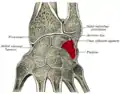

_01_palmar_view.png.webp) Left hand anterior view (palmar view). Triquetral bone shown in red. | |

The triquetral bone (/traɪˈkwɛtrəl, -ˈkwiː-/; also called triquetrum, pyramidal, three-faced, and formerly cuneiform bone) is located in the wrist on the medial side of the proximal row of the carpus between the lunate and pisiform bones. It is on the ulnar side of the hand, but does not directly articulate with the ulna. Instead, it is connected to and articulates with the ulna through the Triangular fibrocartilage disc[1] and ligament, which forms part of the ulnocarpal joint capsule.[2] It connects with the pisiform, hamate, and lunate bones. It is the 2nd most commonly fractured carpal bone.